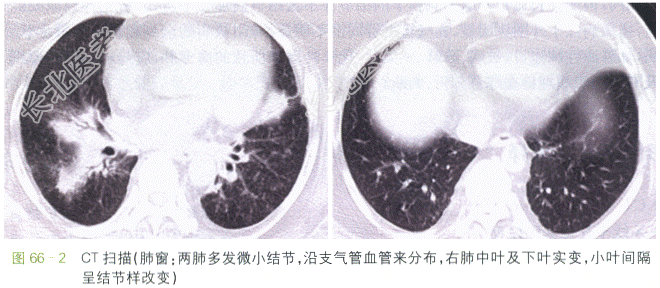

CT扫描肺窗示两肺门增大,肺门旁纹理结构紊乱,可见多个微小点状致密影,沿支气管血管束分布的增厚片状影,叶间裂下明显,可见少量纤维条索。纵隔窗示纵隔内、血管气管旁见大量肿大淋巴结,两侧肺门肿大的淋巴结呈对称分布;增强后可见淋巴结均匀强化,部分可见融合,邻近组织结构受压、移位。